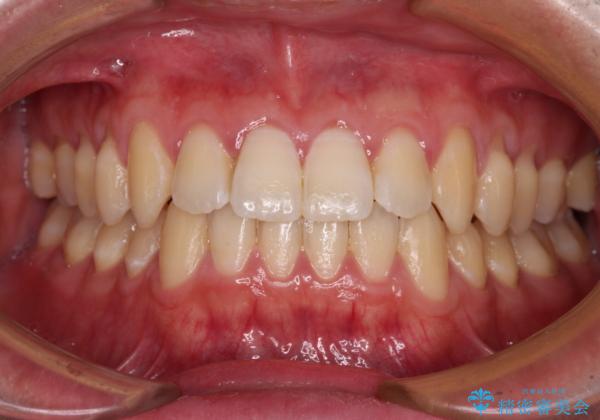

- 上下前歯のデコボコを気にして来院された患者様です。

叢生は軽微であり、費用を抑えて期間もあまりかけずに治療をしたいとのことで、インビザライン・ライトを用いて矯正治療を行うこととしました。

途中通院できなくなり、マウスピースの装着もしっかりとできなかったため、治療期間が長くかかってしまいました。